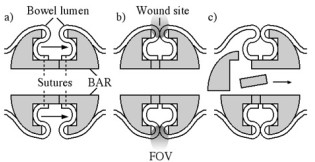

We have demonstrated an early prototype implantable sensor for monitoring surgical wounds after bowel reconstruction. The sensor consists of a coupled pair of 8-element magneto-inductive ring resonators, designed for mounting on a biofragmentable anastomosis ring to give a local increase in signal-to-noise ratio near an annular wound during 1H magnetic resonance imaging. Operation on an anti-symmetric spatial mode is used to avoid coupling to the B1 field during excitation, and a single wired connection is used for MRI signal output. The electrical response and field-of-view have been estimated theoretically. Prototypes have been constructed from flexible elements designed for operation at 1.5 T, electrical responses have been characterized and local SNR enhancement has been confirmed using agar gel phantoms.

| Operation of a biofragmentable anastomosis ring: a) implantation during surgery, b) wound healing and c) breakdown |

| Electrical arrangement of a) single and b) double magneto-inductive ring resonators. |

| Prototype sensor: a) arrangement of thin film circuits before encapsulation; b) mode spectrum obtained by inductive probing. |

| Results of Magnetic resonance imaging at 1.5 T: axial slice images obtained using a) the body coil and b) the sensor; c) variation of SNR with vertical position obtained using the two coils. |